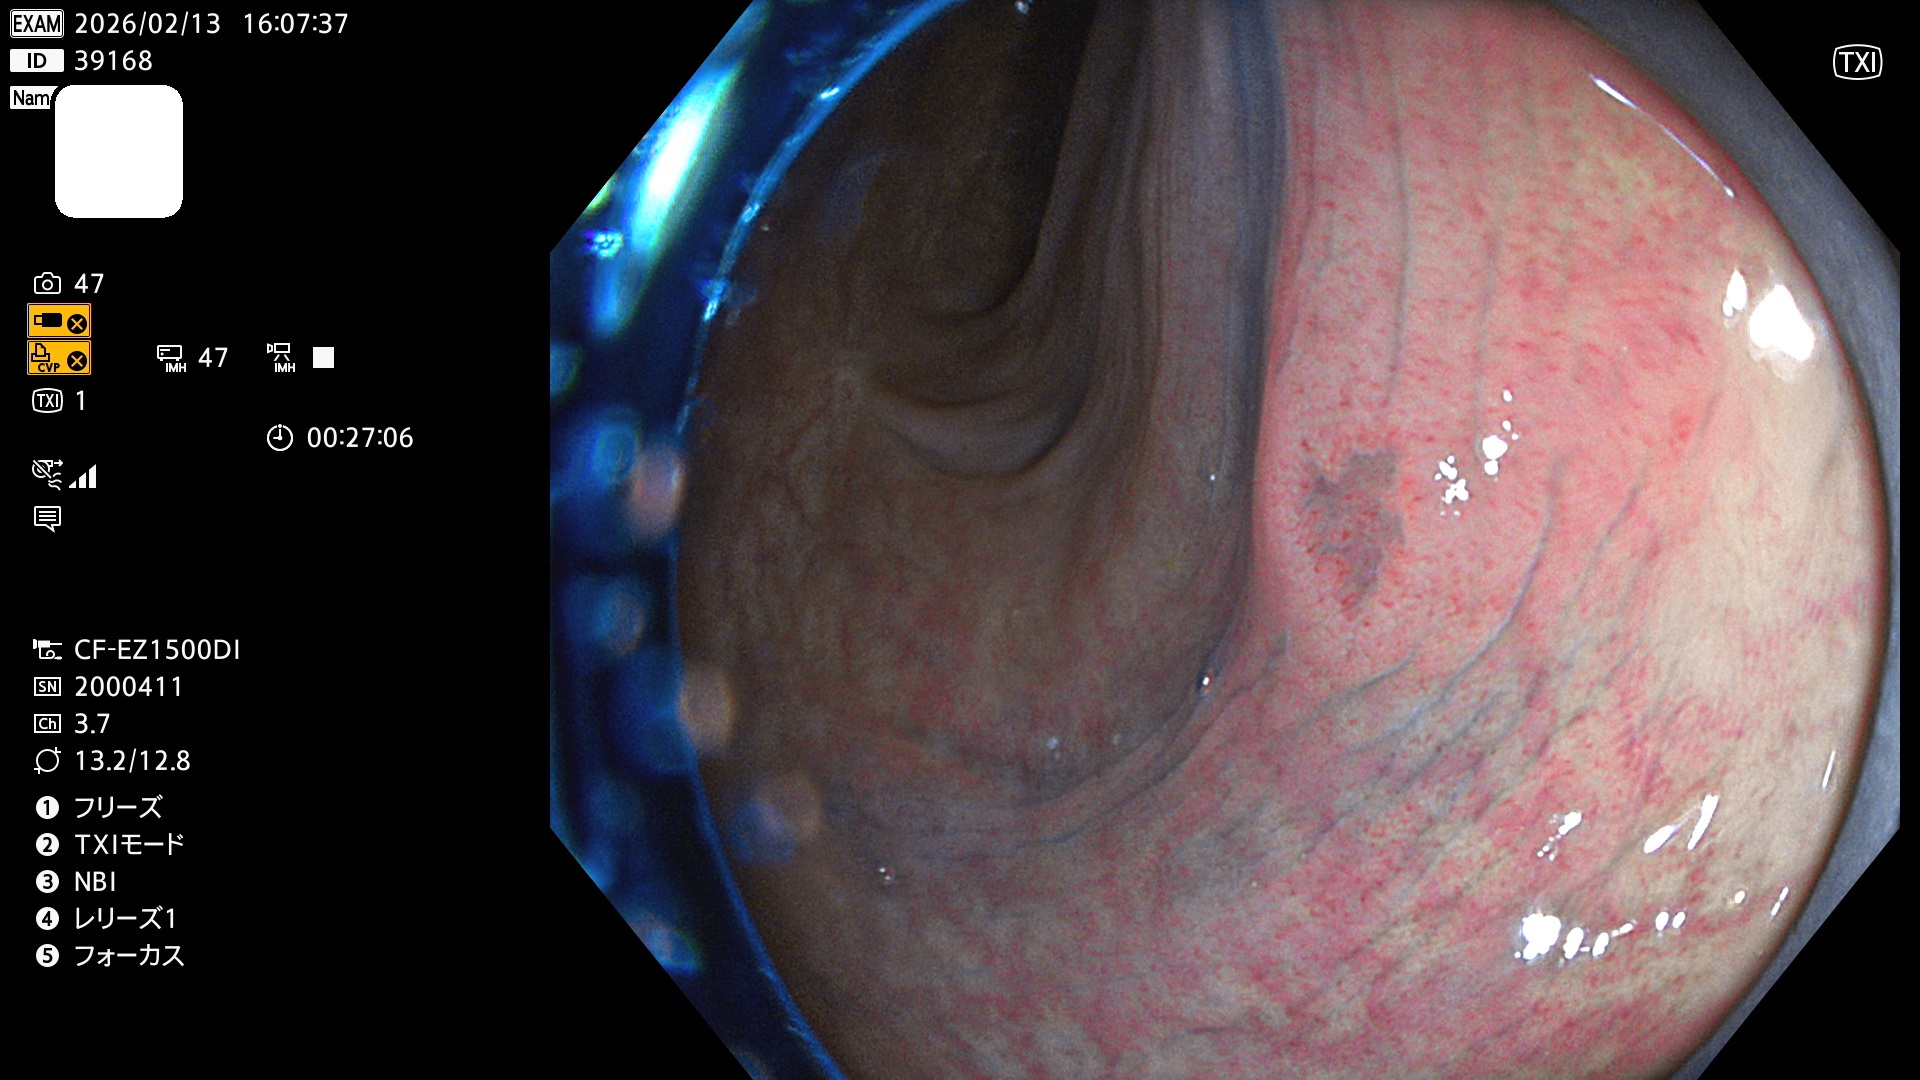

毎週の検査(木・金・土・日)に発見されたUbとUc型・腺腫を、その週の日曜の夜にUPし1週間、提示します。

2026年2月12日〜2月15日の4日間(40件)5個 (Uc_ADR=5個/40人=13%)